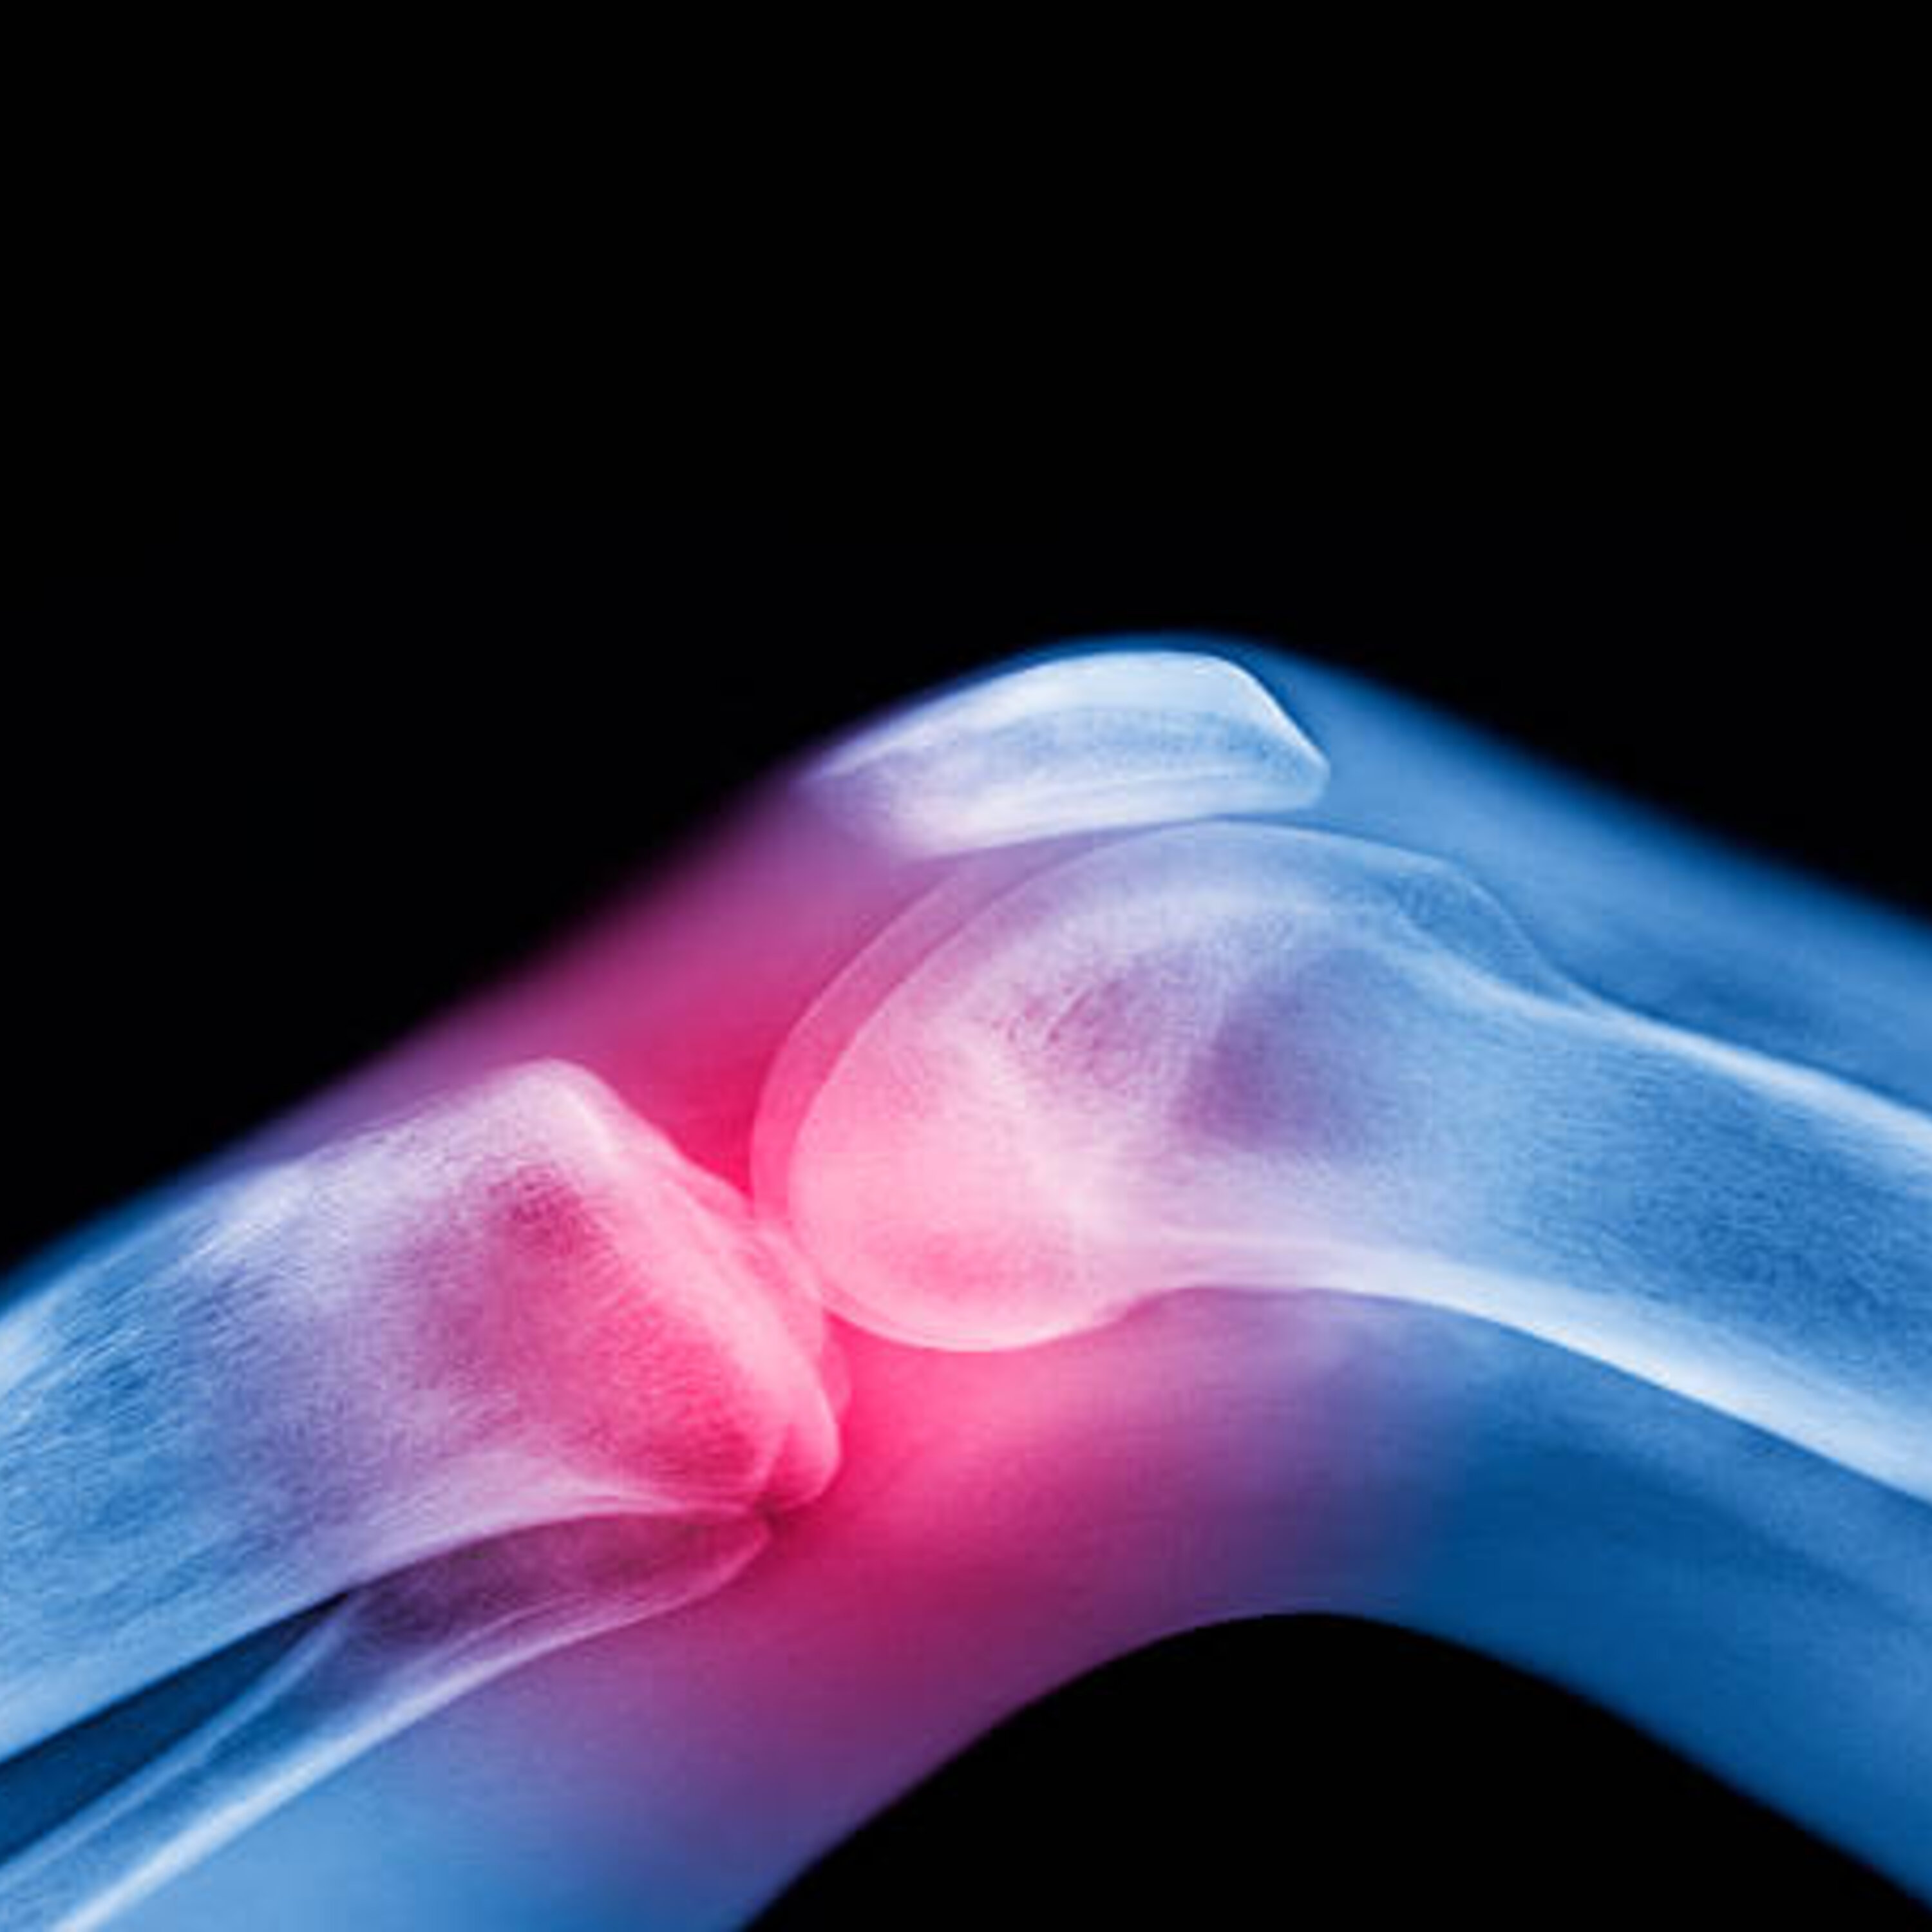

The process for fighting cancer can wreak havoc on bone density and strength. Osteostrong Pittsburgh East Owner, Pamela Wolff, joins Rick to talk about how her company can help people with this issue.